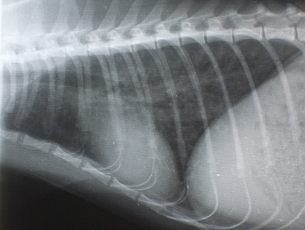

X線検査

気管支パターンが認められます。また横隔膜が斜めになり、暗い肺野の部分が多くなります。時に右の中葉や左の後葉に硬化像が認められます。

| Figure 2. 治療前のX線写真、肺のX線の透過性の亢進と気管支の肥厚を認める | Figure 3. 治療3日後のX線写真、肺の透過性が低下(改善している)している。 |